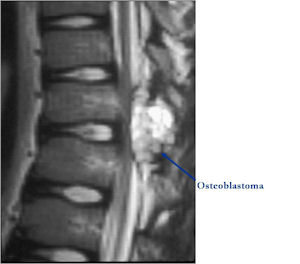

MRI:

- Also useful in determining extent

- There is often extensive edema around the tumor in the surrounding bone and soft tissues that can lead to a misdiagnosis of a malignant tumor.